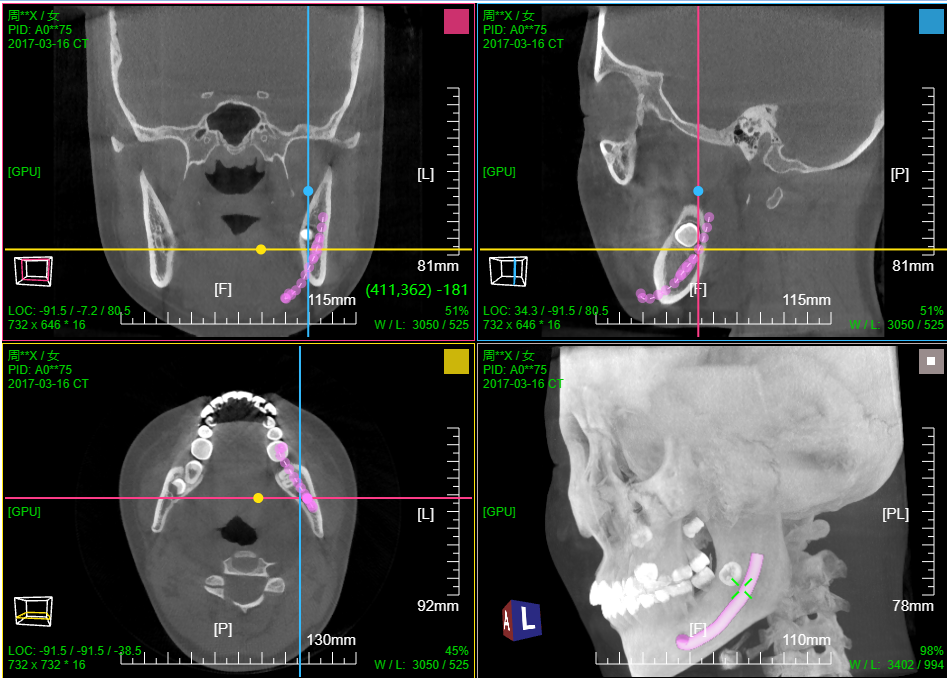

九、牙神经管标记

三维:MPR多平面重建(支持任意旋转)、CPR任意曲线切面重建、MIP最大密度、VR容积重建、VE虚拟内窥;任意三维裁剪、一键去床、一键去头骨、快速旋转、厚切MPR(最大密度/最小密度/均值/VR); 手工/半自动分割,分割目标三维渲染; 肋骨CPR拉伸渲染、牙神经管渲染、血管CPR拉直渲染等